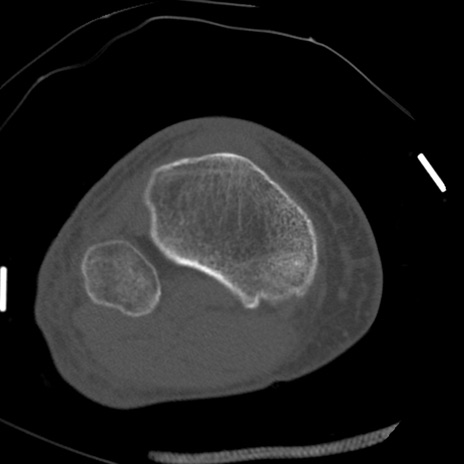

症例28 右膝関節CT(横断像)

右膝関節CT